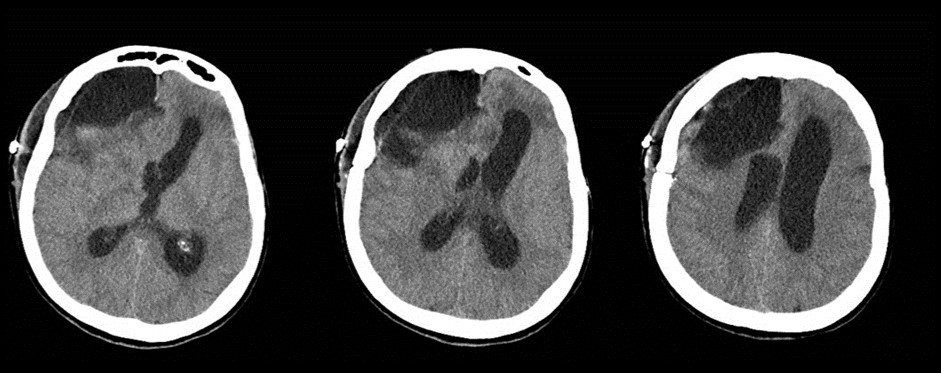

A 65 years-old woman with no relevant medical history was carried to the emergency department of another institution for the sudden onset of headache and vomiting, followed by loss of consciousness. She underwent a cerebral CT scan, that showed diffuse SAH in the basal cisterns and anterior interemispheric fissure (Figure 1). The CT angiogram displayed a single aneurysm of the anterior communicating artery, that local radiologists considered unfavorable for endovascular treatment. The patient was therefore surgically managed, with left pterional craniotomy for aneurysm clipping and right external ventricular drain (EVD) positioning. In the following days the woman reacquired alertness; the EVD was removed without need of permanent shunting and she was transferred to rehabilitation four weeks after the operation in quite good conditions.

Figure 1.Non-contrast axial CT scan showing thick subarachnoid hemorrhage in the basal cisterns and in the frontal interemispheric space

The clinical and radiological features of these two diseases are perfectly known to neurosurgeons; anyhow our case shows that trouble rises when they do occur simultaneously. The patient we described had initially acute signs due to SAH and later signs that were incorrectly interpreted as SAH-related. The tumor was almost invisible -because of its likely small volume and thick SAH- in the first CT performed (Figure 1). Analyzing the early follow-up CT (Figure 2) anyway things do not seem so clear. In the frontal region remained too much fogging close to the midline; the asymmetric distribution of such alteration should had point out a problem, but everybody kept thinking to a “simple” post-hemorrhagic condition, due to ventricular enlargement and focal ischemia. The initial mental impairment of that period was equally attributed to a normal SAH result with moderate hydrocephalus. The proper diagnosis of glioma happened late, and the patient was at that point unable to have significant benefits from surgery.